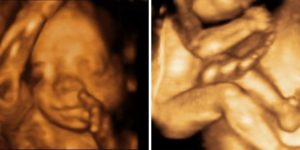

В этот период тело ребенка выглядит полностью сформированным, как показано на фото, но остается слишком худым, поскольку накопление подкожного жира только начинается. Дерма пока остается красной и морщинистой, на головке появляется пушок.

Во время УЗИ мама может увидеть, что:

- конечности стали пропорциональными;

- на пальцах есть ногти;

- у ребенка открыты глаза, если он не спит (он уже может различать свет и темноту);

- черты лица немного непривычные, угловатые;

- он может закрывать руками лицо, сосать палец, сжимать кулаки, гримасничать.

После оценки параметров доктор записывает информацию в карту пациентки и определяет возможность естественного родоразрешения. Во время проведения УЗИ родители смогут понаблюдать за своим малышом на 23 неделе развития. Некоторые клиники предлагают сделать видео этого исследования.